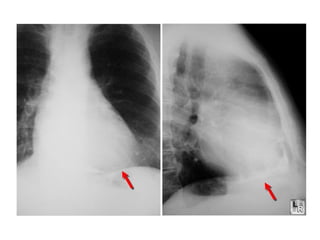

   Pericardial calcification is seen in a minority of patients and should raise the

suspicion of tuberculous pericarditis, but calcification per se is not diagnostic of

constrictive physiology.

   The lateral chest film is useful to detect pericardial calcification along the right

heart border and in the atrioventricular groove.

Chest radiograph showing marked pericardial calcifications

in a patient with constrictive pericarditis.